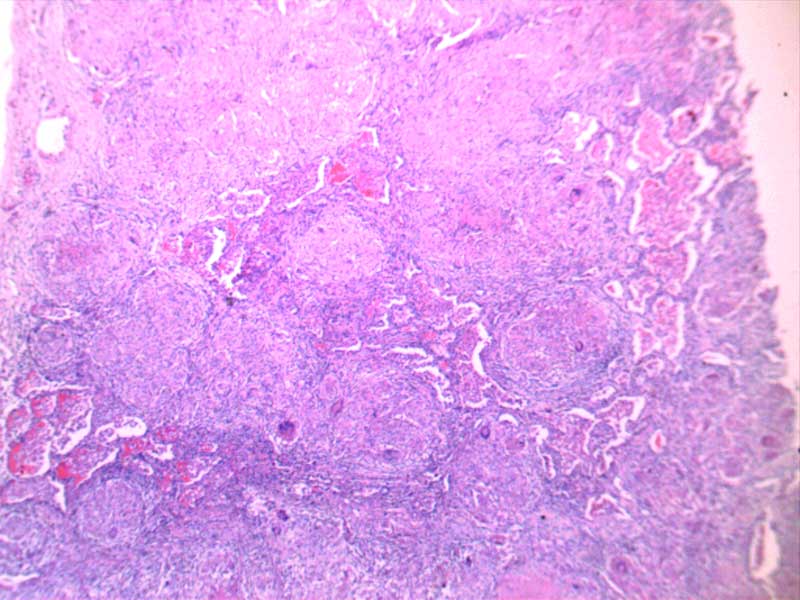

神经鞘瘤-10倍

肾透明细胞癌-10倍

肾细胞水肿-4倍

粟粒性肺结核

透明血栓-10倍

纤维肉瘤10-倍

纤维素性胸膜炎

小叶性肺炎-10倍-(2)

新月体肾炎-(2)

异物性炎-10倍

主动脉粥样硬化-4倍

主动脉粥样硬化-10倍